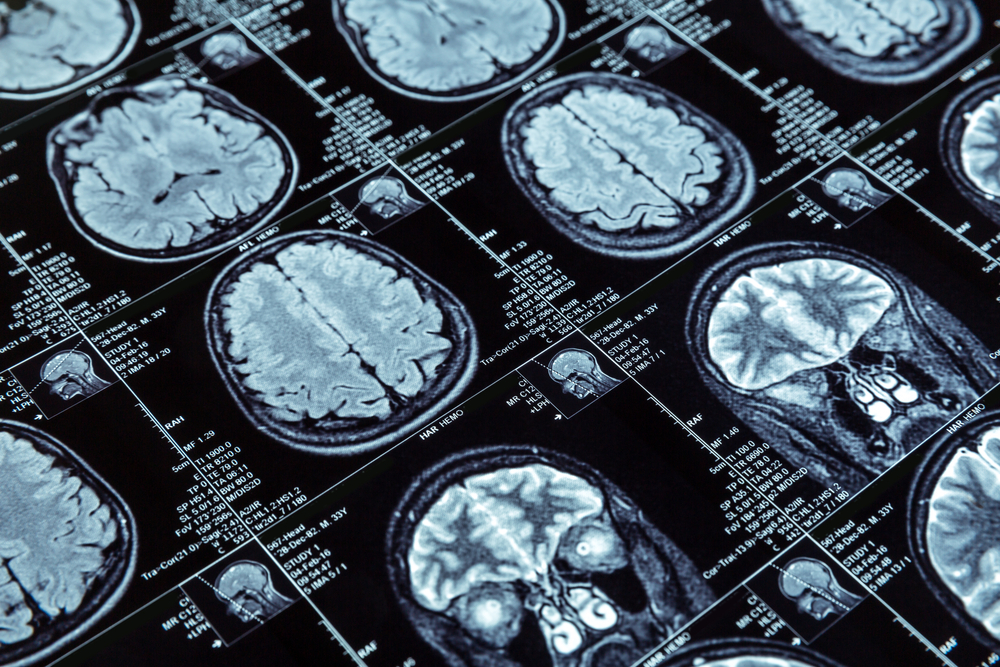

Магнитно-резонансная томография — эффективная диагностическая процедура, позволяющая получать отчетливое изображение в различных плоскостях, не перемещая при этом пациента, не меняя его положения. Эта особенность бывает очень ценной, например, при диагностике повреждений в случае тяжелых травм.

В отличие от компьютерной томографии (КТ), метод позволяет визуализировать не только рентгеноконтрастные ткани и объекты. На снимках, сделанных при помощи МРТ, видна структура и мягких тканей.

К минусам этой методики можно отнести медленное формирование изображения (на реконструкцию картинки в каждой из плоскостей может уходить от 5 до 10 минут). Поэтому качественное изображение может формироваться только при полной неподвижности. С этой точки зрения, большое значение имеет дисциплинированность обследуемого, ведь каждое движение сказывается на качестве снимка.